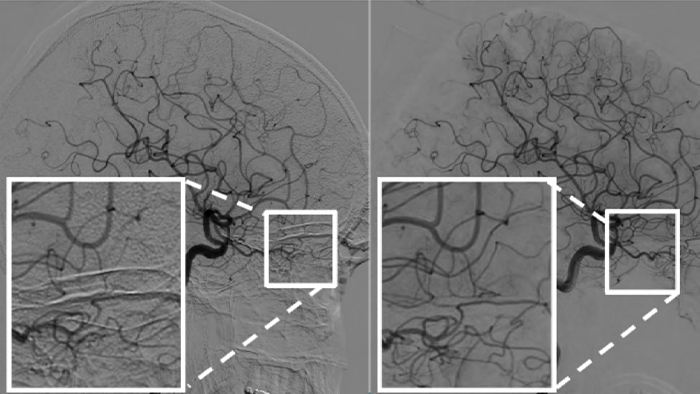

液体塞栓物質とアーチファクトを区別

AVMを経時的にモニタリングする場合、サブトラクションアーチファクトが臨床情報のように見える場合があります。フィリップスのClarityIQリアルタイムオートピクセルシフトにより、誤解を招く可能性のある情報をユーザーの操作なしにリアルタイムで除去することができます。

液体塞栓物質の方向と到達を確認

治療中、サブトラクションアーチファクトにより、液体塞栓剤の進行方向が不明瞭になる場合があります。ClarityIQでリアルタイムオートピクセルシフトを使用すると、液体塞栓剤の進行方向と到達を視覚化できます。